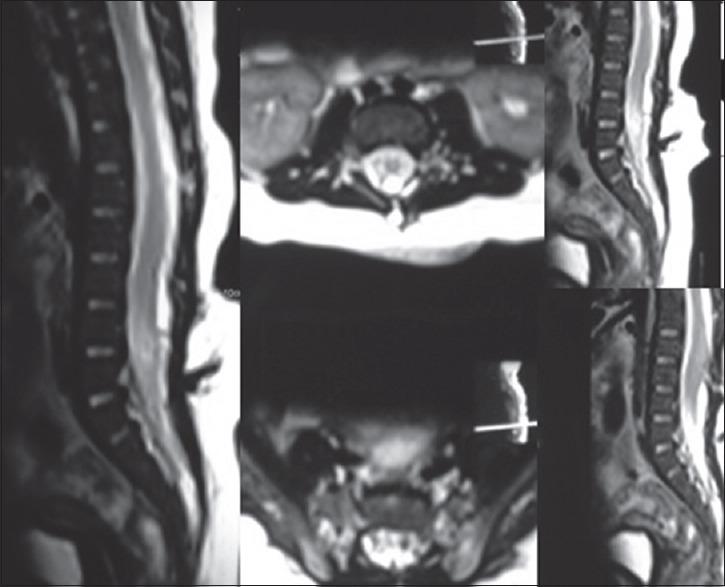

Teratomas are one of the most common tumors in newborn with excellent prognosis arises from totipotent primordial germ cells harboring two or three germ cell layers. The tumor has been titled "Great masquerade." The teratomas of sacrococcygeal region present with lower limb weakness, urinary or bowel obstruction, and swelling at lower back or intrauterine mass in ultrasound or complicated delivery. A 2-month-old male child presented with complaints of swelling over lumbosacral region with discharging punctum since birth. Sagittal T2-weighted magnetic resonance imaging (MRI) of the spine showed myelocele at L5 level forming placode with central defect at L4-S1 and low-lying tethered cord up to L4-L5. The patient was operated, and histopathology surprisingly came to be mature teratoma. We followed the patient with serum beta human chorionic gonadotropin and alpha-fetoprotein markers and MRI. Literature supports complete surgical removal, including coccyx and tumor base. Mature teratoma is considered as benign disease thus even subtotal excision is appropriate but with aggressive follow-up. The difference in recurrence following total compared to subtotal resection is considered insignificant. In this article, we have discussed the management of teratoma in detail. Teratoma with meningomyelocele is a rare entity. There is still dilemma in managing cases and prognosticating parents in such patients. The provisional diagnosis of teratoma should also be considered when child presents as midline sacrococcygeal mass.